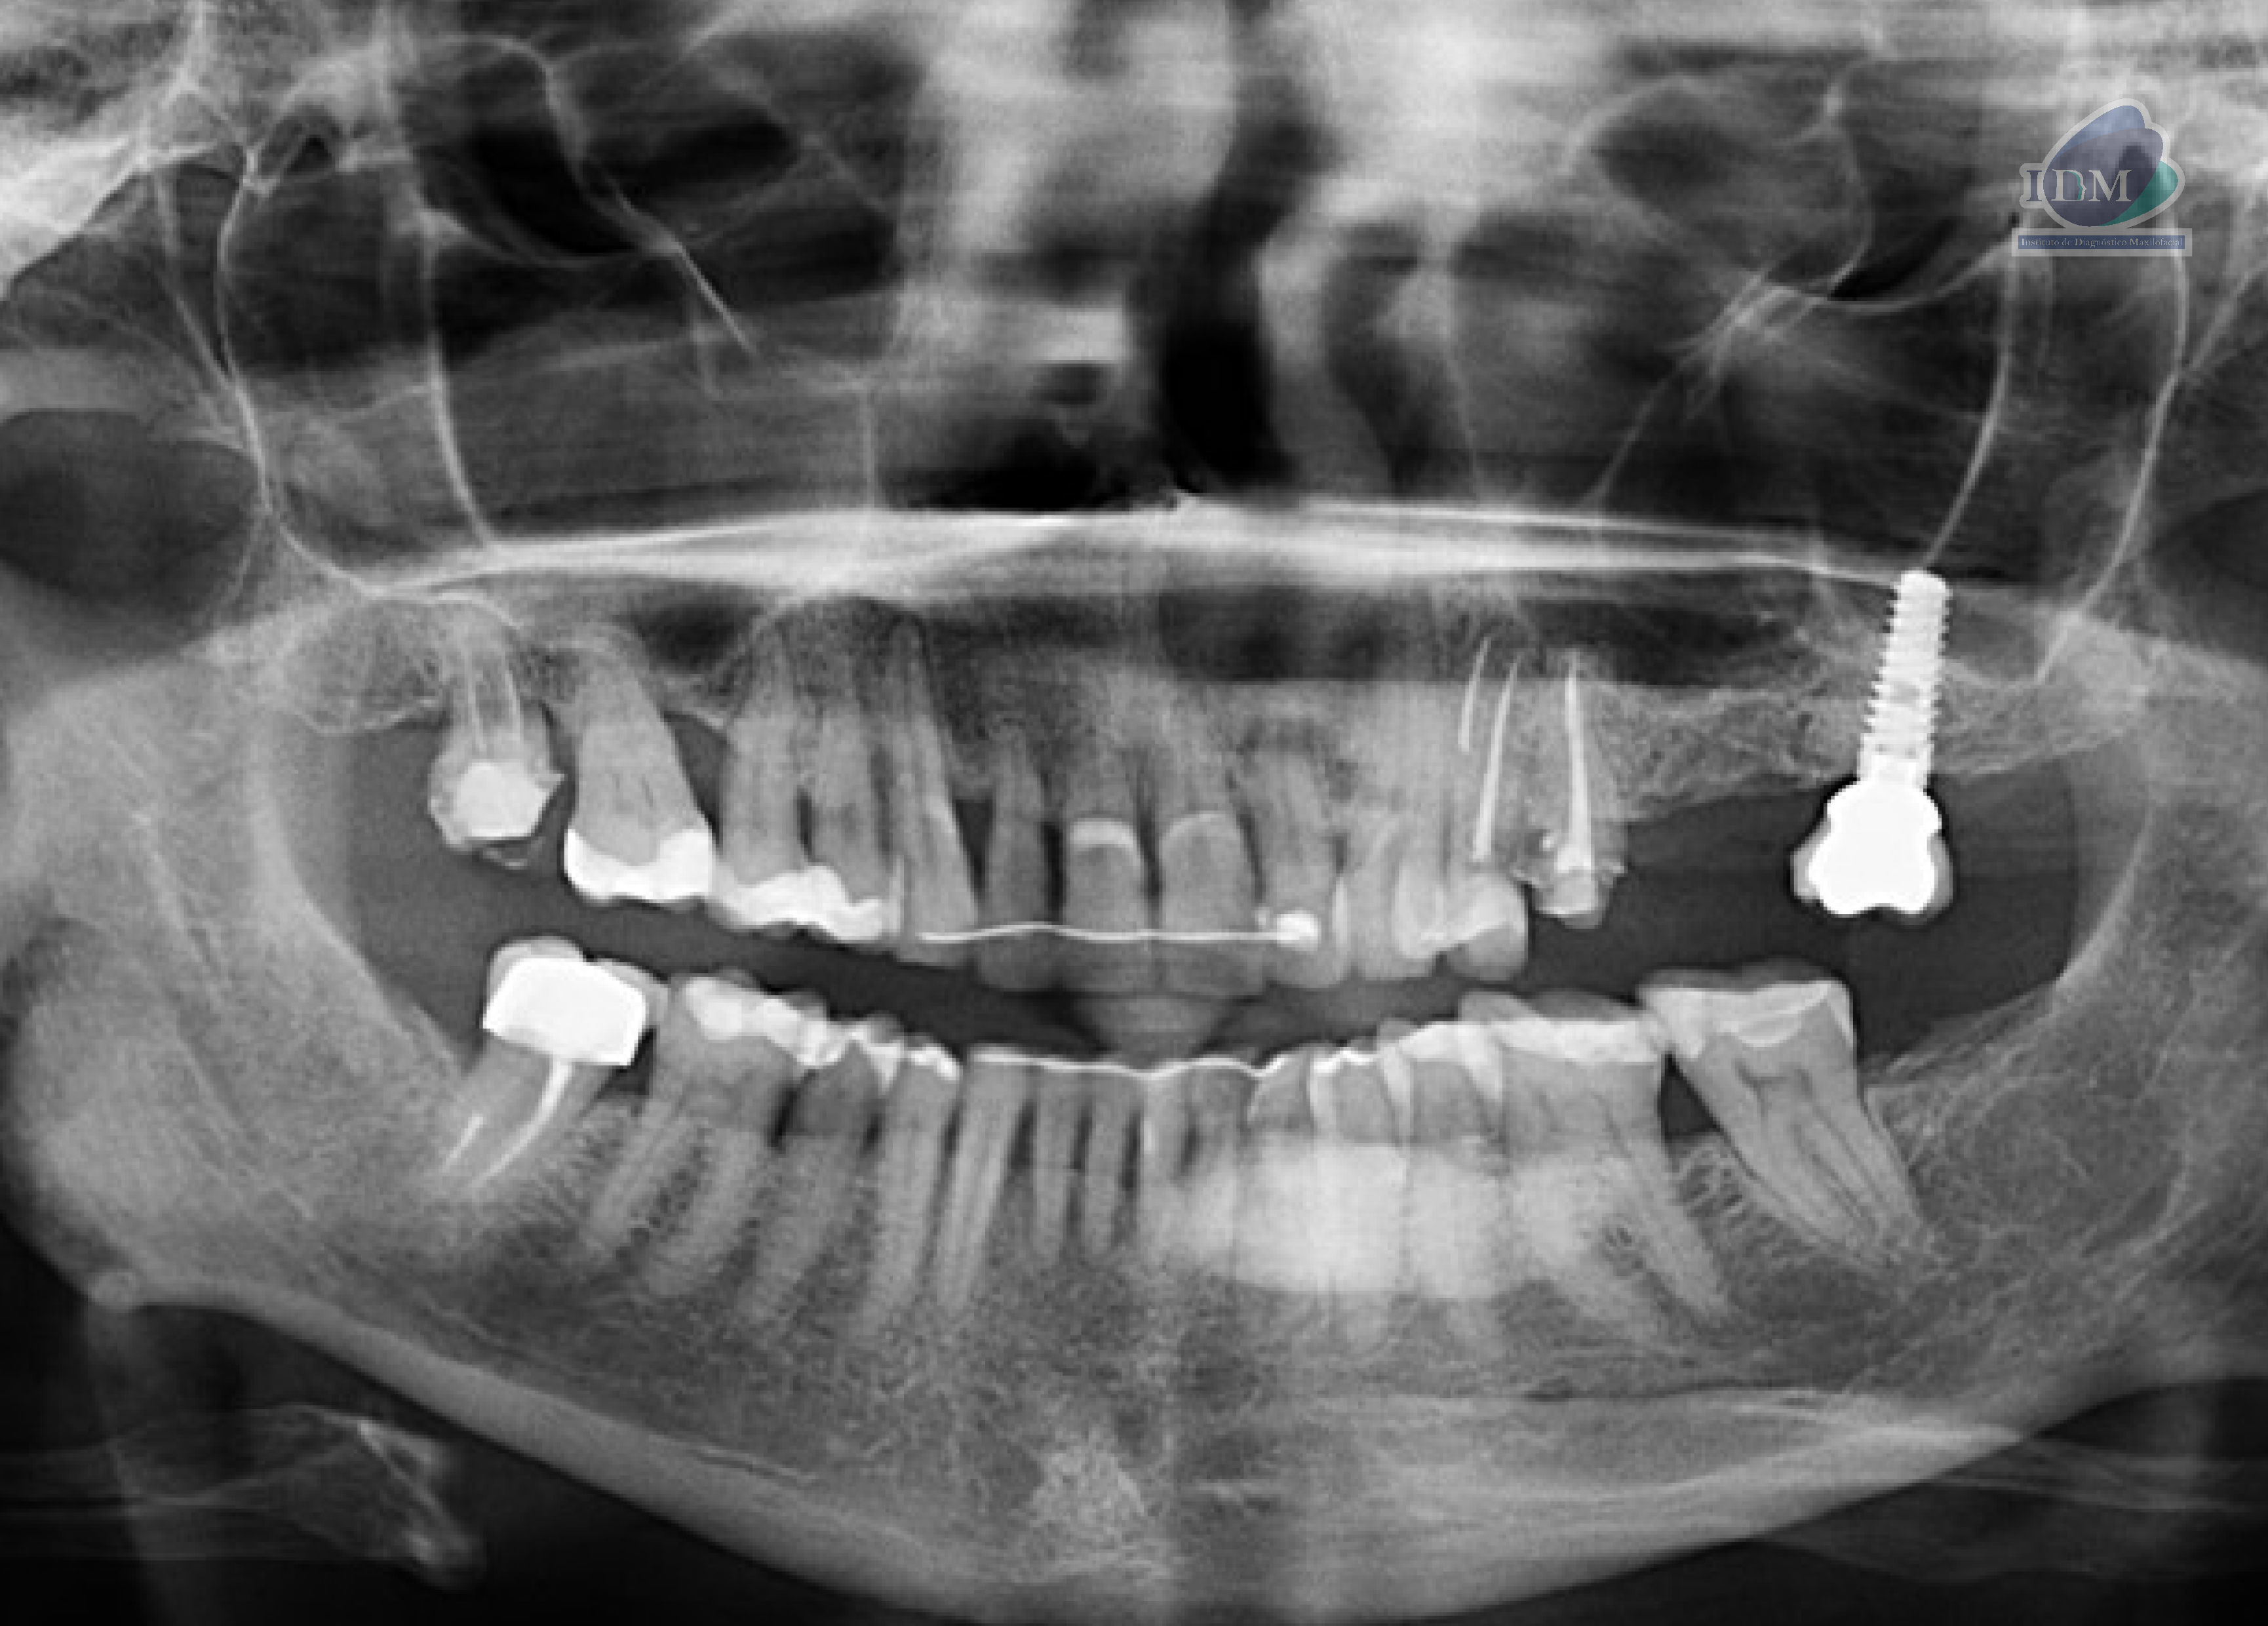

Paciente femenina de 65 años acude al centro para una tomografía de cráneo completo para una evaluación general. A la evaluación de la radiografía panorámica se observa aplanamiento y erosión del contorno condilar bilateral que ocasiona la presencia de osteofito en el cóndilo del lado derecho compatible con un proceso degenerativo articular. Asimismo, se observa la neumatización de ambos senos maxilares, la reabsorción ósea moderada del proceso alveolar, la presencia de dispositivo de ferulización en piezas anterosuperiores y anteroinferiores, múltiples restauraciones coronarias, tratamiento de conductos en las piezas 18 y 47, presencia de implante dental con corona protésica en zona de pieza 27. Finalmente se observa una imagen radiopaca difusa de forma irregular que se proyecta en cuerpo mandibular del lado izquierdo sobre la porción radicular de la pieza 32 hasta la pieza 36.

Radiografia Panorámica